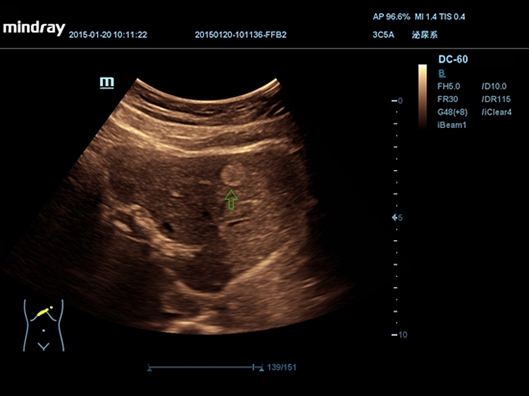

Mindray DC-55 обладает особым преимуществом - независимо от физической конституции пациента и плотности тканей, он обеспечивает высокое качество изображений без нежелательной зернистости. Это достигается благодаря использованию специальной технологии формирования мульти-луча и режима тканевого доплера с количественным анализом.

• Конвексный датчик Mindray 3C5A